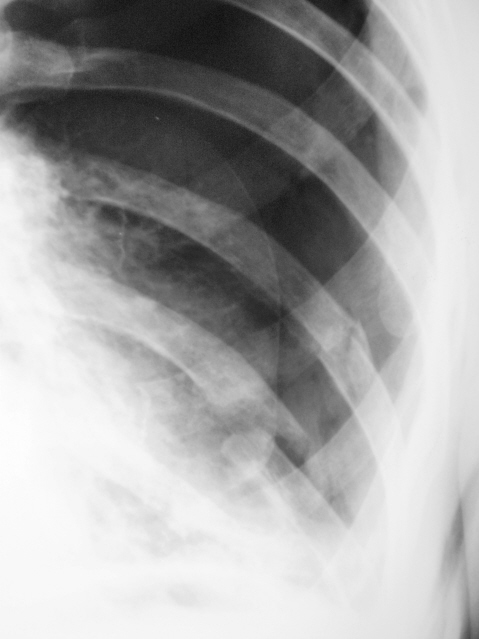

Обзорная рентгенограмма (а): выраженная эмфизема легкого, легочные поля повышенной прозрачности, межреберные промежутки расширены, ребра располагаются горизонтально, диафрагма низко. Легочное сердце. На прицельной томограмме (б) в области верхушки левого легкого видны тонкостенные буллы, их наружные стенки не определяются.